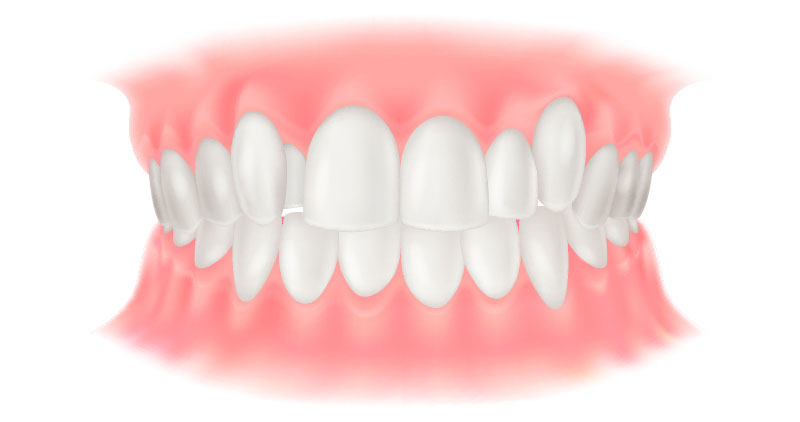

矯正歯科は、歯並びや噛み合わせを整える治療です。見た目の改善に加え、噛みやすさや磨きやすさが向上することで、むし歯や歯周病の予防にもつながります。また、噛み合わせが原因で歯周病が進行したり、歯が割れる、補綴物が壊れるといったトラブルが起きている場合には、その改善策として矯正治療を提案することもあります。

矯正歯科